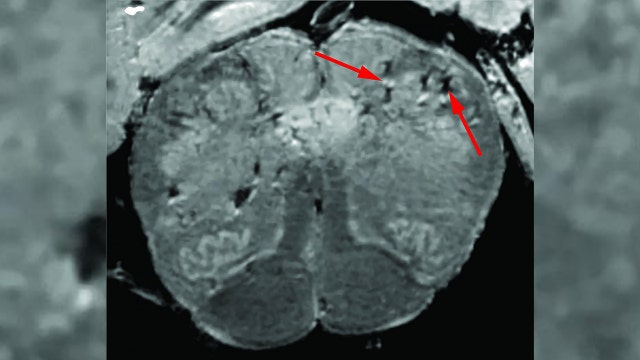

NIH launches online database to track, understand neurological symptoms associated with COVID-19

Amid increasing evidence of lasting neurological effects from COVID-19, the National Institutes of Health said it has launched an online database in order to track these symptoms in hopes of better understanding how the coronavirus impacts the brain and nervous system.